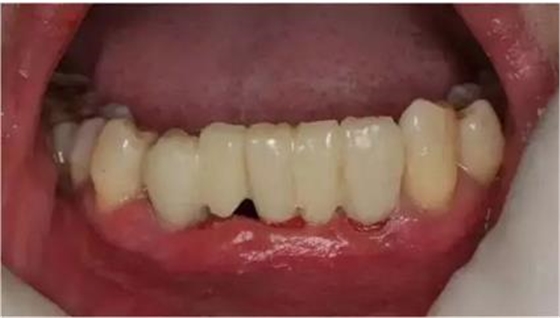

臨時(shí)冠就位,即刻修復(fù),無咬合接觸

總結(jié)

1:本病例的難度在于高骨密度

的條件下如何順利植入植體

2:數(shù)字化修復(fù)時(shí),

種植臨時(shí)修復(fù)體可能難以就位,

特別是多顆牙的修復(fù)

來源:滿毅副教授